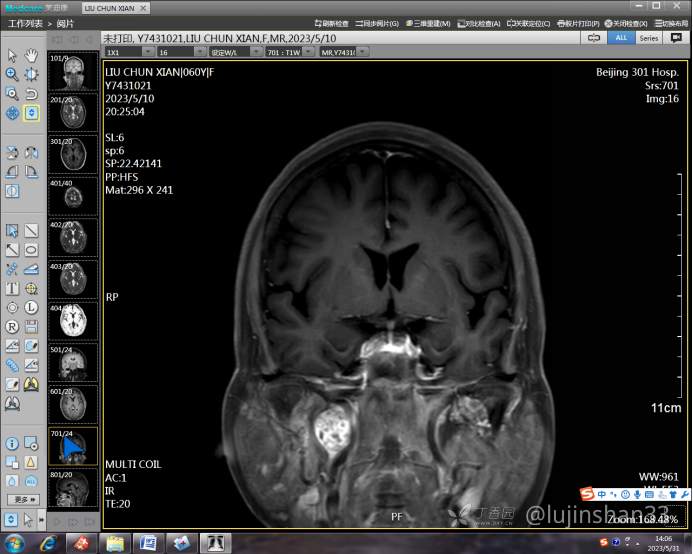

术后复查MRI: